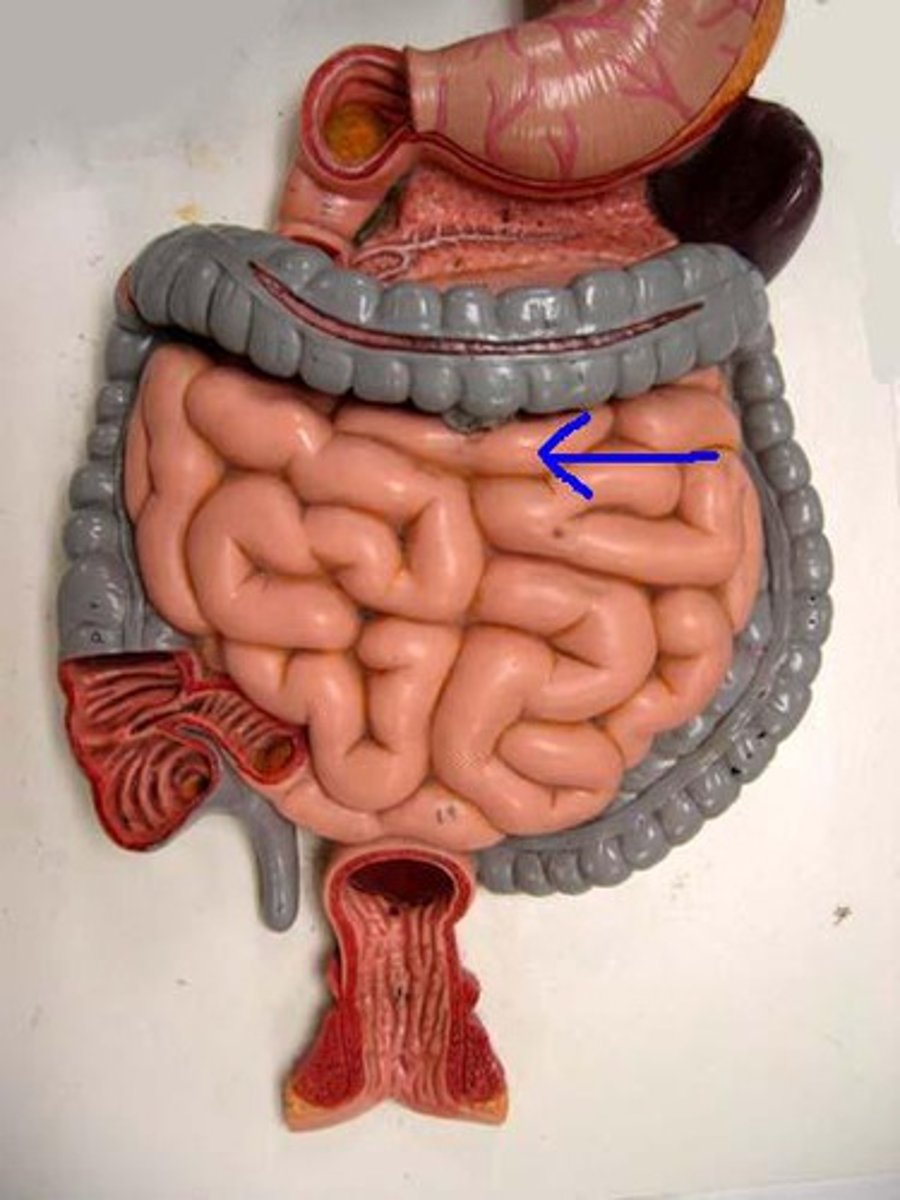

duodenum

jejunum

ileum

mesentery

large intestine

cecum

cecum

ascending colon

transverse colon

descending colon

sigmoid colon

illeocecal valve

Apendix

haustrum / haustra

taeniae coli

rectum